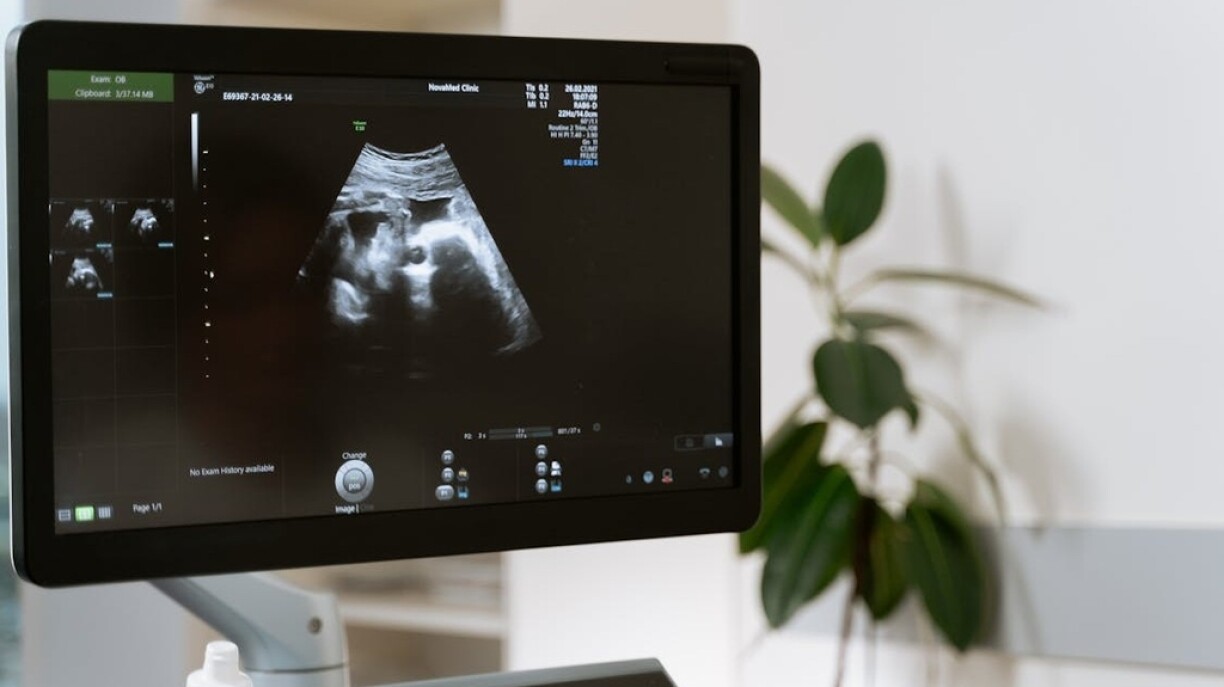

Provided you had a positive pregnancy test, your first visit is around the second and third month of the pregnancy. Although there is so much excitement initially that you expect the ball to start rolling right away, they do need you to be at least a couple of weeks further along to be able to see heart activity in the ultrasound.

Important tests are then done at 12-14 weeks of your pregnancy, the T1 ultrasound can tell if there are any malformations as well as determine a more definite length of your pregnancy. You will also be invited to do the NIPT test, which is also reimbursed by CNS, and there is a blood test which screens for Down Syndrome.